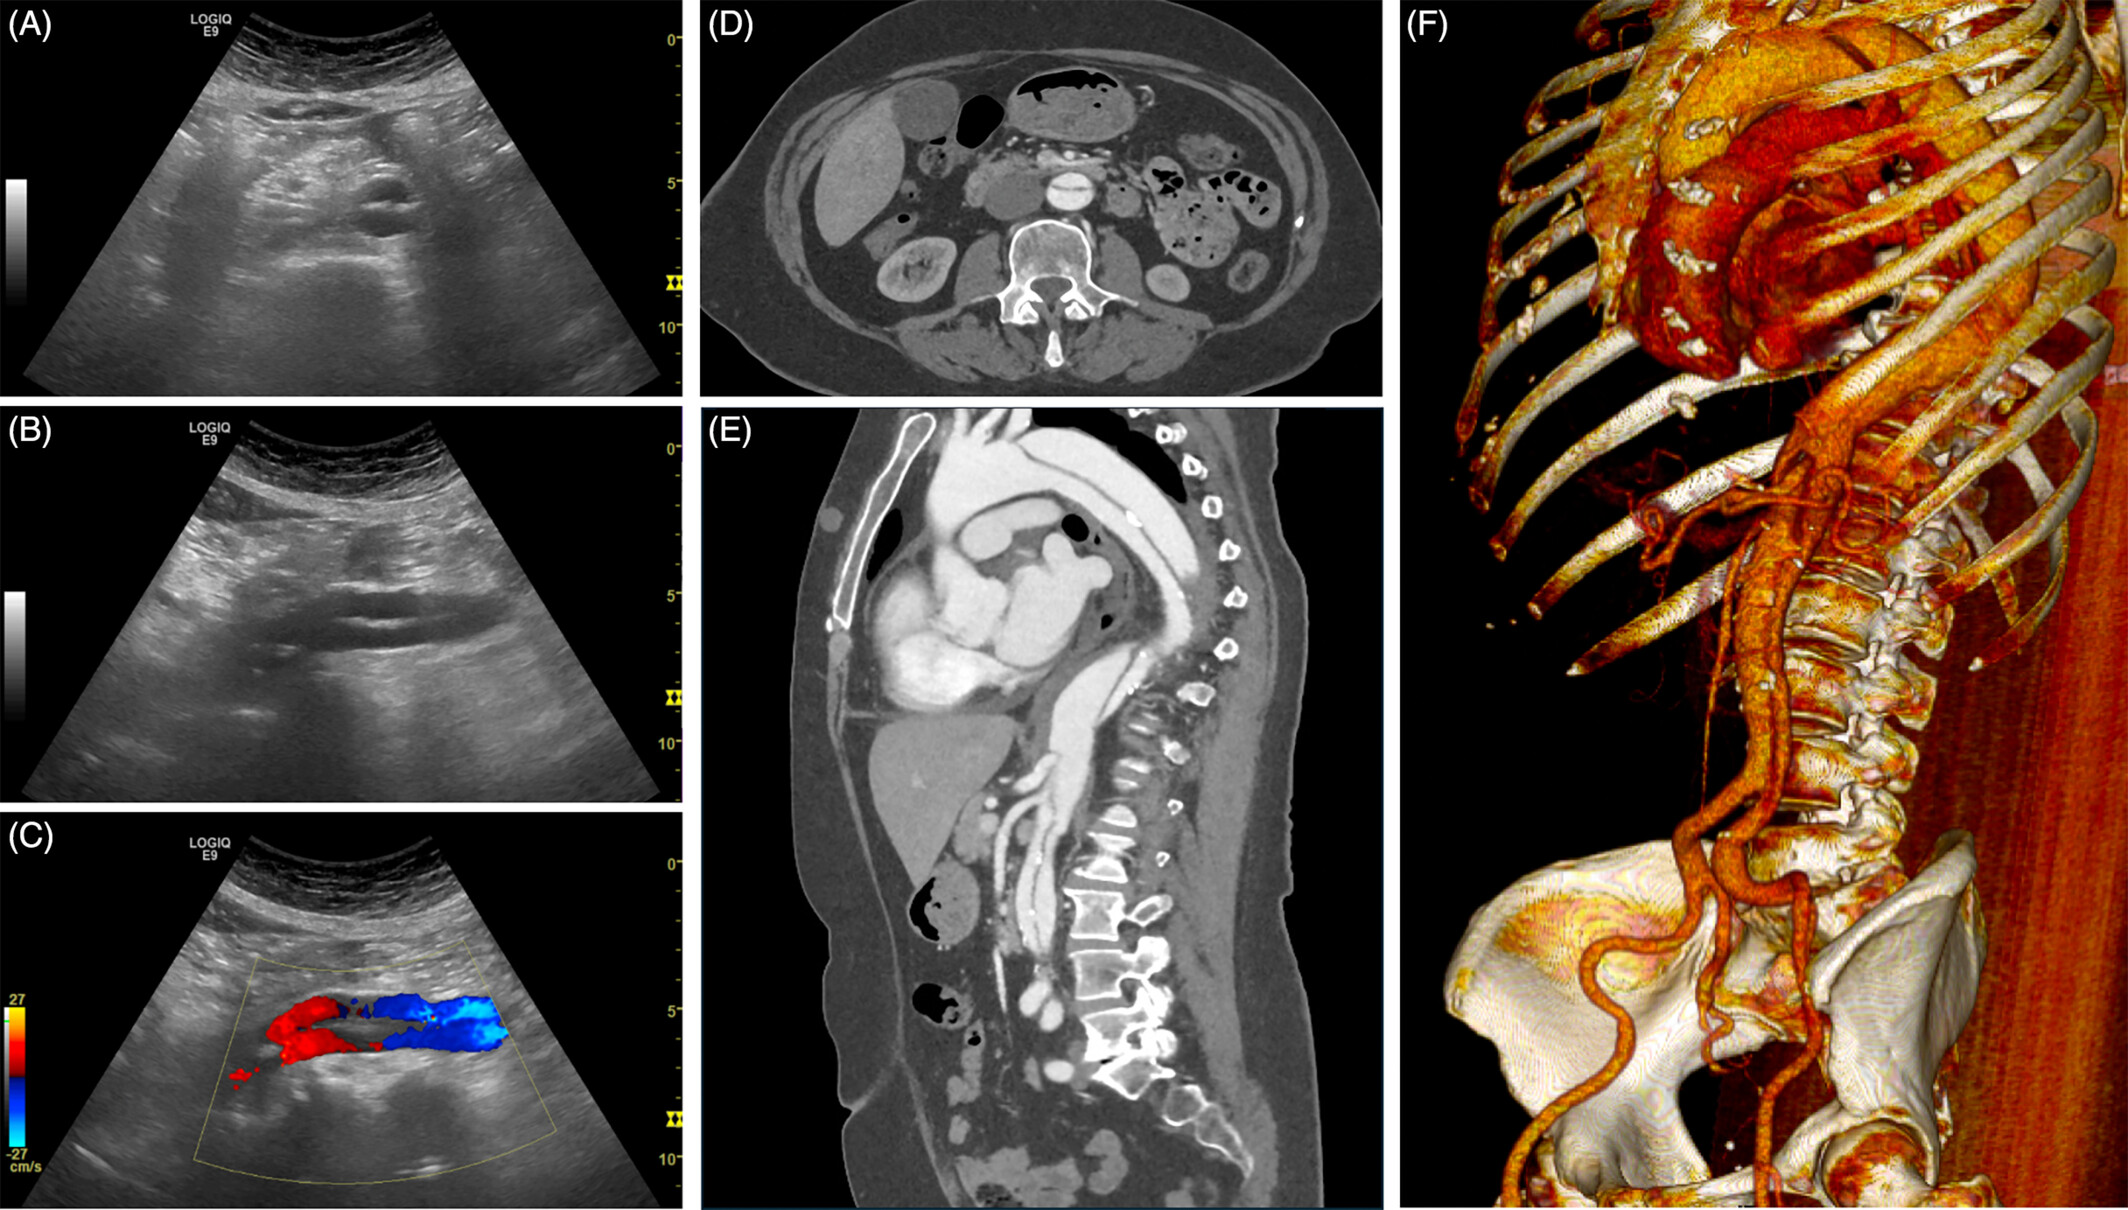

복부 대동맥 초음파 검사는 방사선 노출 없이 짧은 시간에 혈관 직경·벽 구조·혈류를 확인할 수 있어 응급상황을 예방하는 1차 선별검사로 각광받고 있습니다.

복부 대동맥류(AAA)

- 직경 3 cm 이상, 또는 정상 대비 50% 이상 확장된 상태를 말합니다.

- 5.5 cm 이상이면 파열 위험이 급격히 증가하므로 수술·스텐트 삽입을 검토합니다.

- 흉통·등통증이 번개처럼 발생하며, 초음파는 내막 판막(intimal flap)과 혈류 차이를 즉시 확인해 조기 진단이 가능합니다.

- 초음파 도플러(Modified Bernoulli)로 혈류 속도를 계산해 협착률을 추정합니다.

검사 방법과 준비 사항

- 금식 6–8 시간: 장내 가스 제거로 영상 선명도 확보.

- 검사 자세: 하늘보기를 기본으로, 필요 시 좌·우측 측위를 병행.

- 검사 시간: 15–30 분. 통증·방사선 노출 없음.

- 결과 확인: 직경·혈류 속도·벽 두께를 실시간 확인, 검사 종료 후 즉시 설명 가능.